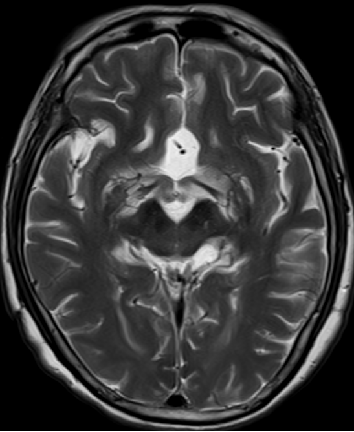

2013-8-2 MRI

2013-5-16 MRI

2013-5-16

2013-8-2

2014-12-13

2015-4-1